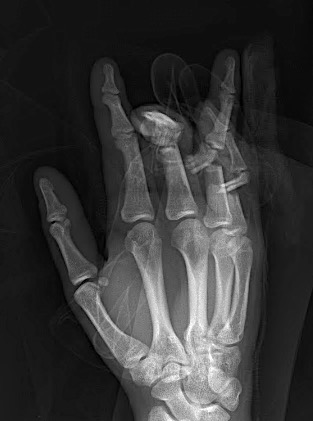

Case 2:

A 20-year-old male suffered a complex multi-digit injury of the right hand requiring revascularization and stabilization of both proximal phalanx and PIP joint fractures (Figs 5 - 8). Multiple plates, including the rotation correction plate from the 1.5 module of the VA Locking Hand System were used for fixation. The Variable Angle Locking system is ideal when only two screws, either proximal or distal, are able to be inserted due to space limitation.

One major advantage of variable angle technology in very distal phalangeal fractures is the ability to be extremely flexible with a wide range of fixation options. Freedom of implant placement assists early mobilization, vital in these complex fractures with associated soft-tissue trauma.